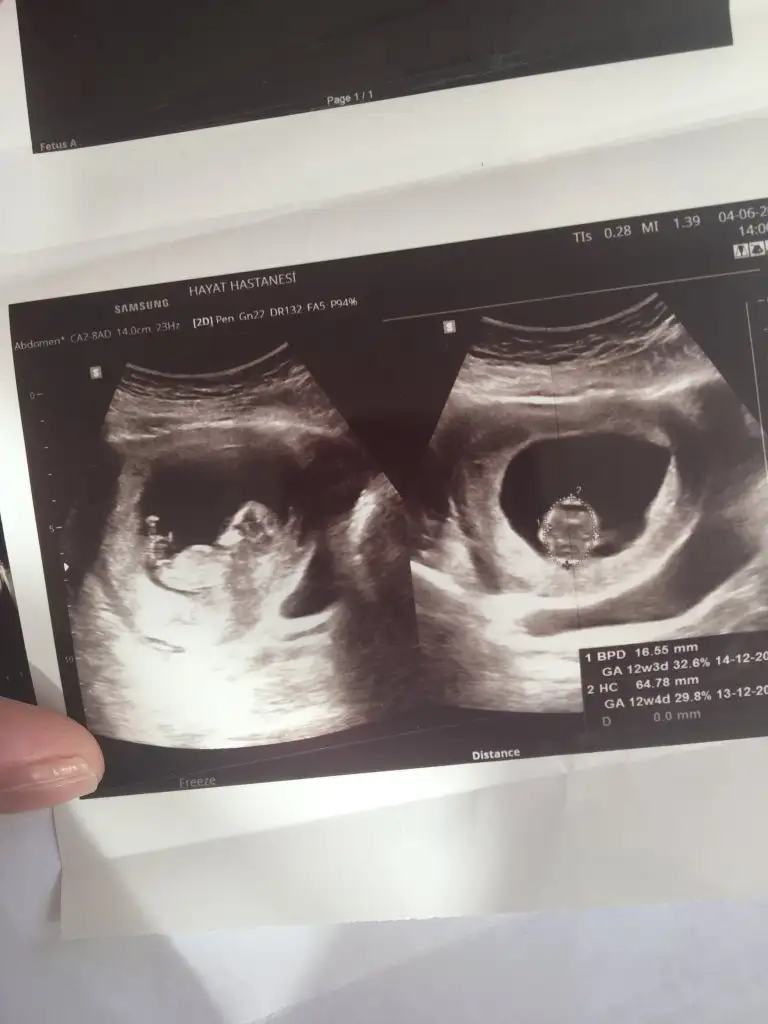

Mrb 13 haftalik olduk cok sukurKız gibi net de değil kız sanki 12-13 olunca tekrar usg paylaşın

Kız gibiMrb 13 haftalik olduk cok sukur

Nub için 11 12 13 hafta olmalıBir oglumuz var bir kızımız olsun cok istiyoruz tabiki öncelik sağlık

Kız gibi

bu da diger acidan fotografi ayagi kapatmis gibi amabu bu haftaki goruntusu 12. hafta gecen hafta erkek demistiniz ama emin olamamistiniz@ikrameyra